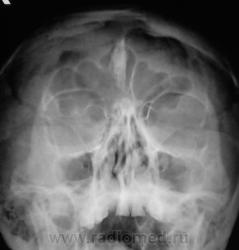

Обызвествление серповидного отростка.

А, меня, что-то смутила чешуя лобной кости...

Действительно, лобная кость какая-то "кучерявая", а в боковой проекции не доснимали?

Вены широковаты и боковые лакуны также выражены. Возможно на фоне остеопороза. Возраст, вероятно, немолодой.

Гиперпневматизация лобных пазух. Обызвествление серповидного отростка. Вероятно, повышение внутричерепного давления (сосудистый рисунок). Искривление носовой перегородки вправоsmiley. На нижнюю треть верхнечелюстных пазух "наслоились" пирамиды височных костей.